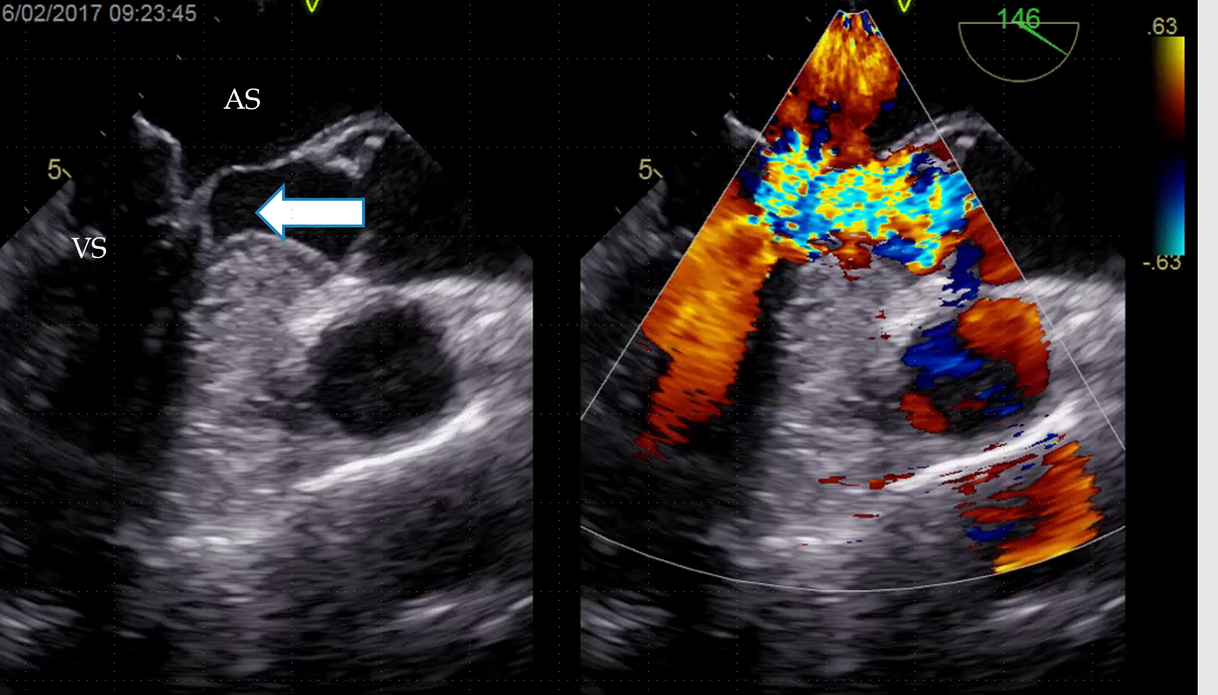

Obstrucția la ieșirea sângelui din VS se datorează atât îngroșării (hipetrofiei) mușchiului cardiac exact în această zonă, cât și modificărilor anatomice ale valvei mitrale. Modificările valvei mitrale fac ca valva să fie practic absorbită în calea jetului de sânge ce iese din inimă, accentuând obstrucția și făcând ca valva să nu se mai închidă eficient, determinând apariția regurgitării mitrale. Astfel, pe lânga faptul ca sângele iese cu dificultate din ventricul, o parte din el refluează înapoi de unde a venit, adică în atriul stâng (AS). De aceea, eliminarea obstrucției se realizează cel mai bine chirurgical, printr-o intervenție care realizează atât îndepartarea mușchiului în exces (miectomia), cât și repararea modificărilor valvulare mitrale (plastia valvei mitrale).

Figura 1. Obstrucția ieșirii sângelui din VS (săgeată) O parte din sânge se întoarce in AS, determinând apariția regurgitării mitrale.